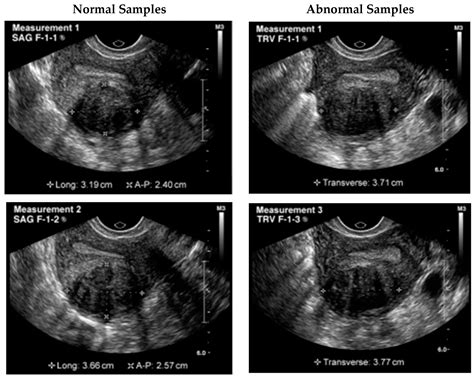

Uterus Test Videos often delve into these conditions, explaining their symptoms, causes, and diagnostic methods. For instance, a video might show how a transvaginal ultrasound is used to detect uterine fibroids or how a biopsy is performed to diagnose uterine cancer.

• Ultrasound: Uses sound waves to create images of the uterus and surrounding structures.